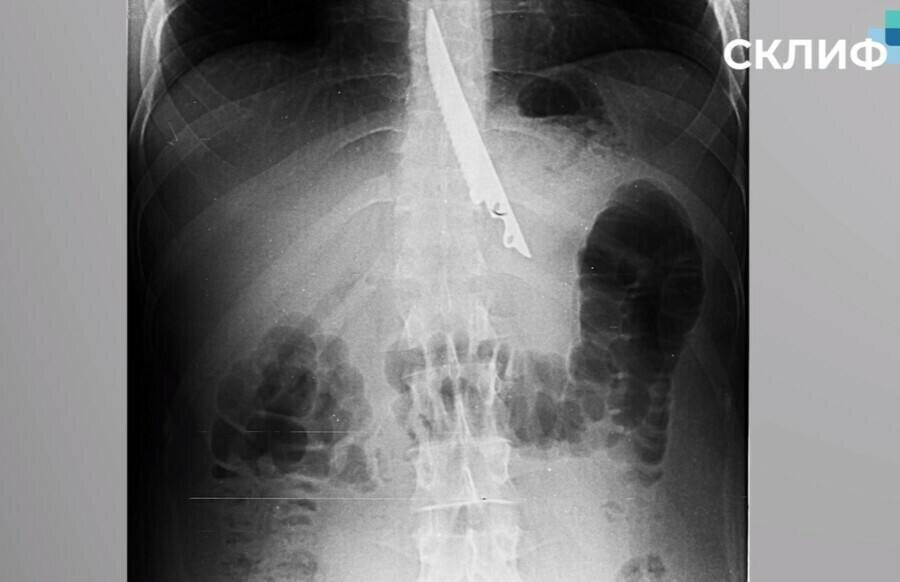

Мужчина подавился шашлыком и проглотил нож

Не так давно в СМИ публиковалась история мужчины, который проглотил нож. Он находился на отдыхе и подавился шашлыком. Один из его друзей решил протолкнуть застрявшее мясо ножом, после чего мужчина случайно нож проглотил. Честно говоря, я бы не поверил в историю, если бы к ней не был приложен рентгеновский снимок. Нож был проглочен ручкой вперёд. Что ж, стало понятней...